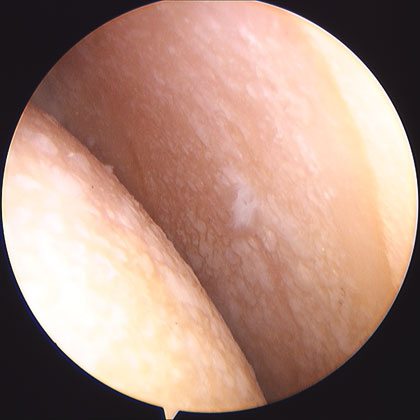

shoulder joint picture

Normal shoulder joint arthroscopic image.